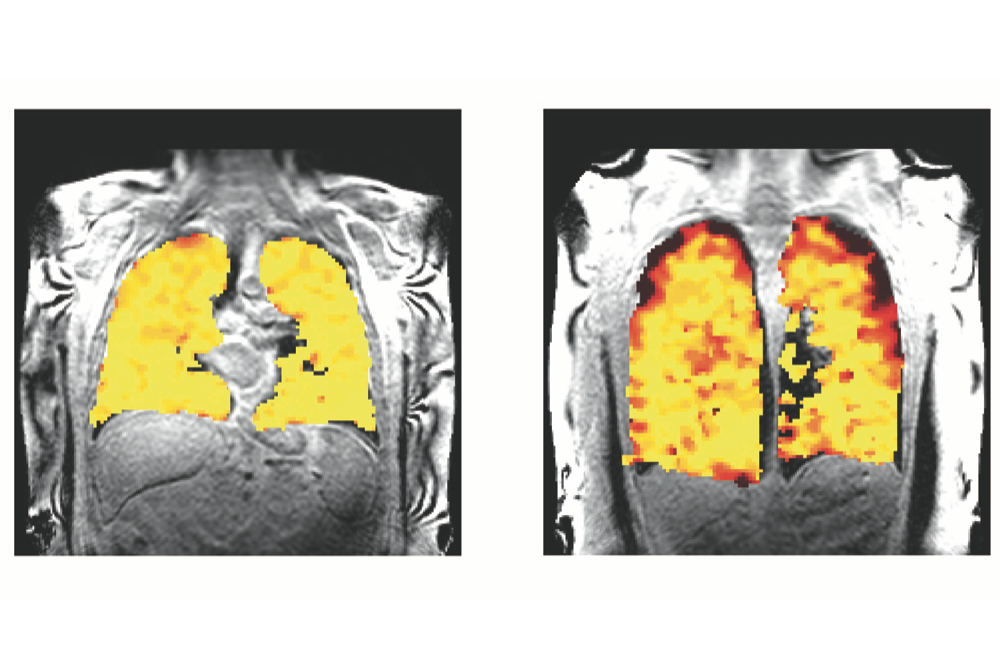

Example case shows advantages of DWI sequence in detecting a mass hidden inside atelectasis. CT chest, PET-CT, T2 BLADE, and DWI are compared for a 72-year-old male patient with a satellite nodule (red arrow) obscured by atelectasis adjacent to the dominant right upper lobe mass (yellow arrow) in CT. However, DWI image demonstrates restricted diffusion (orange yellow) corresponding to focal FDG uptake (blue arrow) within the satellite nodule.